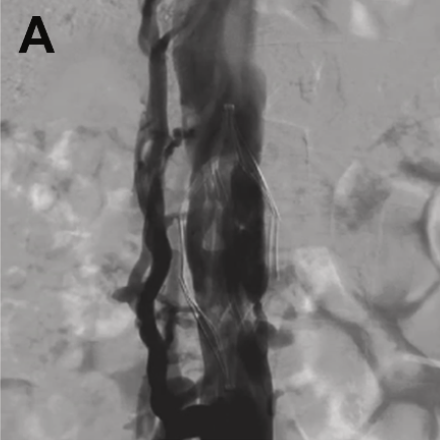

Better visualization, smarter planning. In this JVS-VL pilot study, CEUS + UHFUS showed promise for improving preop mapping and streamlining LVA in patients with lymphedema.